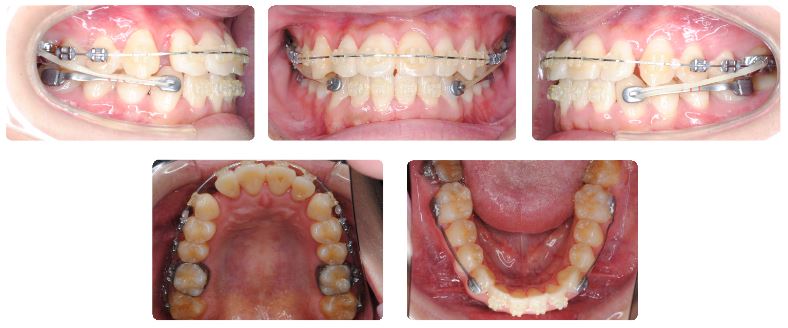

カリエールモーション装着から3か月後です。

上顎前歯にみられるスペースは依然認められますが、上顎前歯の突き上げ感が改善されてきています。

下顎左側のカリエールモーションの後ろが脱離していますが、すぐに再装着しました。

カリエールモーション装着して5か月後の状態です。

上顎は幅径を広げるためにバイパスの拡大装置が装着されています。

下顎にはスペースがみられるようになりました。